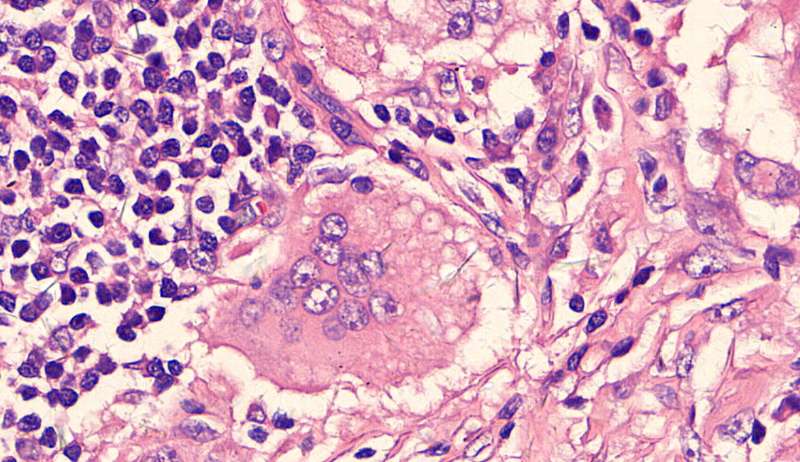

最后发一例化脓性炎症

中性粒细胞很多,此处组织结构破坏

左侧液化,脓肿壁较规则平滑

周围的炎症机化区

破坏力在这里逐渐减弱

逐渐从中性粒细胞转为淋巴细胞为主

周边区:

肺泡内有渗出,逐渐吸收 机化是不是纤维细胞增多看的?王:是的